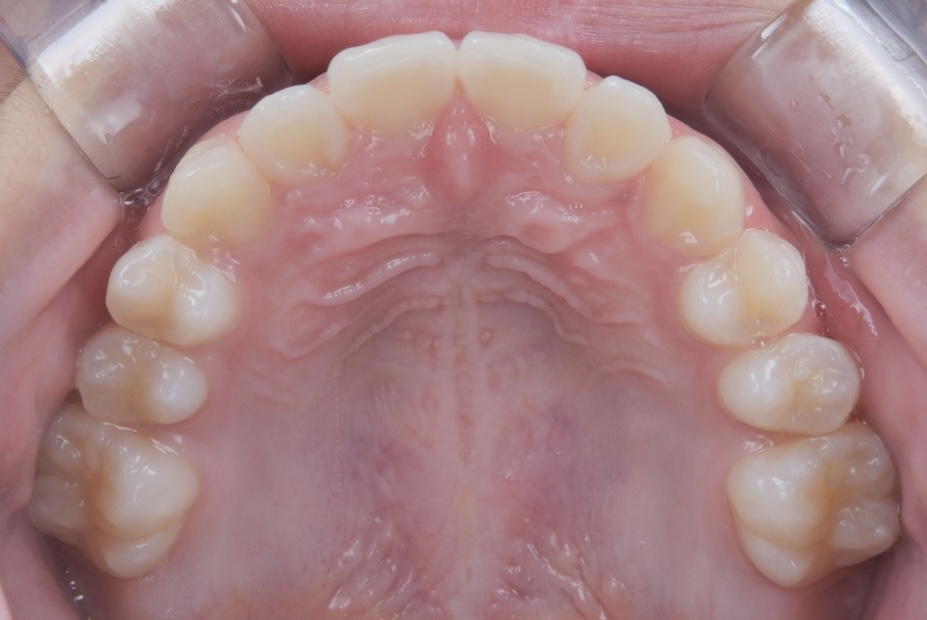

After 1

After 2

After 3